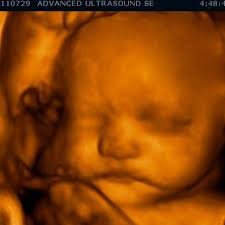

For this reason 3D ultrasound reconstruction of the nasal bone and other facial bones is useful. At this stage the babys legs arms fingers and toes should be fully formed. Mothers should not be encouraged to have an ultrasound called a.

Of the many defects 3D 4D ultrasound has been useful in evaluating the skeletal and cardiovascular systems in fetuses with this condition. But keeping tabs on your babys growth can be a good thing and knowledge is power. By combining the results of the two parts of the test it is possible to identify if a pregnant woman is at increased risk of having a baby with Down syndrome.